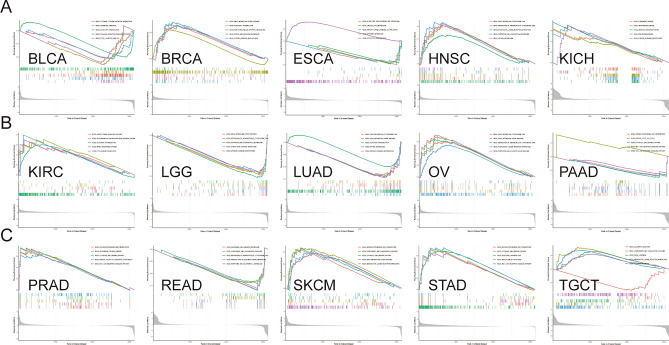

GSEA

GSEA was utilized to examine the biological function of HS6ST2 in cancers. Gene sets from Kyoto Encyclopedia of Genes and Genomes (KEGG) and Gene Ontology (GO) were retrieved from the GSEA database28. The R package "Cluster Profiler" was used to conduct both studies.

Functional analysis of HS6ST2

To ascertain the biological character of HS6ST2 in a range of tumor tissues, GSEA was performed. The resulting GO function is shown in Fig. 12. The data revealed a positive correlation of HS6ST2 with the detection of chemical stimuli in breast invasive carcinoma, lymphoid neoplasm diffuse large b-cell lymphoma, esophageal carcinoma, kidney renal clear cell carcinoma, liver hepatocellular carcinoma, sarcoma, stomach adenocarcinoma, kidney renal papillary cell carcinoma, and rectum adenocarcinoma, but the correlation was negative in lung squamous cell carcinoma. Similarly, GO BP analysis revealed a favorably correlation between HS6ST2 expression and ncRNA processing in adrenocortical carcinoma, kidney renal clear cell carcinoma, kidney renal papillary cell carcinoma, prostate adenocarcinoma, cervical squamous cell carcinoma and endocervical adenocarcinoma, and rectum adenocarcinoma. As seen in Fig. 12B,G, HS6ST2 correlated favorably with the degree to which genes were silenced in uterine corpus endometrial carcinoma, uveal melanoma, lymphoid neoplasm diffuse large b-cell lymphoma, and esophageal carcinoma. In contrast, HS6ST2 was negatively correlated with epithelial cell differentiation in lung adenocarcinoma, but the correlation was positive in cholangiocarcinoma and mesothelioma.

The top five KEGG pathways significantly connected with HS6ST2 expression in each tumor are shown in Fig. 13. Positive correlations were found between HS6ST2 expression and the cytosolic DNA sensing pathway and antigen processing and presentation in prostate adenocarcinoma, skin cutaneous melanoma, and stomach adenocarcinoma, but the correlations were negative in pancreatic adenocarcinoma. In contrast, in rectum adenocarcinoma and brain lower grade glioma, HS6ST2 expression was inversely correlated with the porphyrin and chlorophyll metabolism pathways and the metabolism of xenobiotics by cytochrome P450, while the correlation was positive in head and neck squamous cell carcinoma. As shown in Fig. 13A,B, the Toll-like receptor signaling pathway was negatively correlated with HS6ST2 expression in bladder urothelial carcinoma and pancreatic adenocarcinoma. In addition, HS6ST2 was favorably connected with steroid hormone biosynthesis and drug metabolism in breast invasive carcinoma, while the correlation was negative in lung adenocarcinoma and brain lower grade glioma.